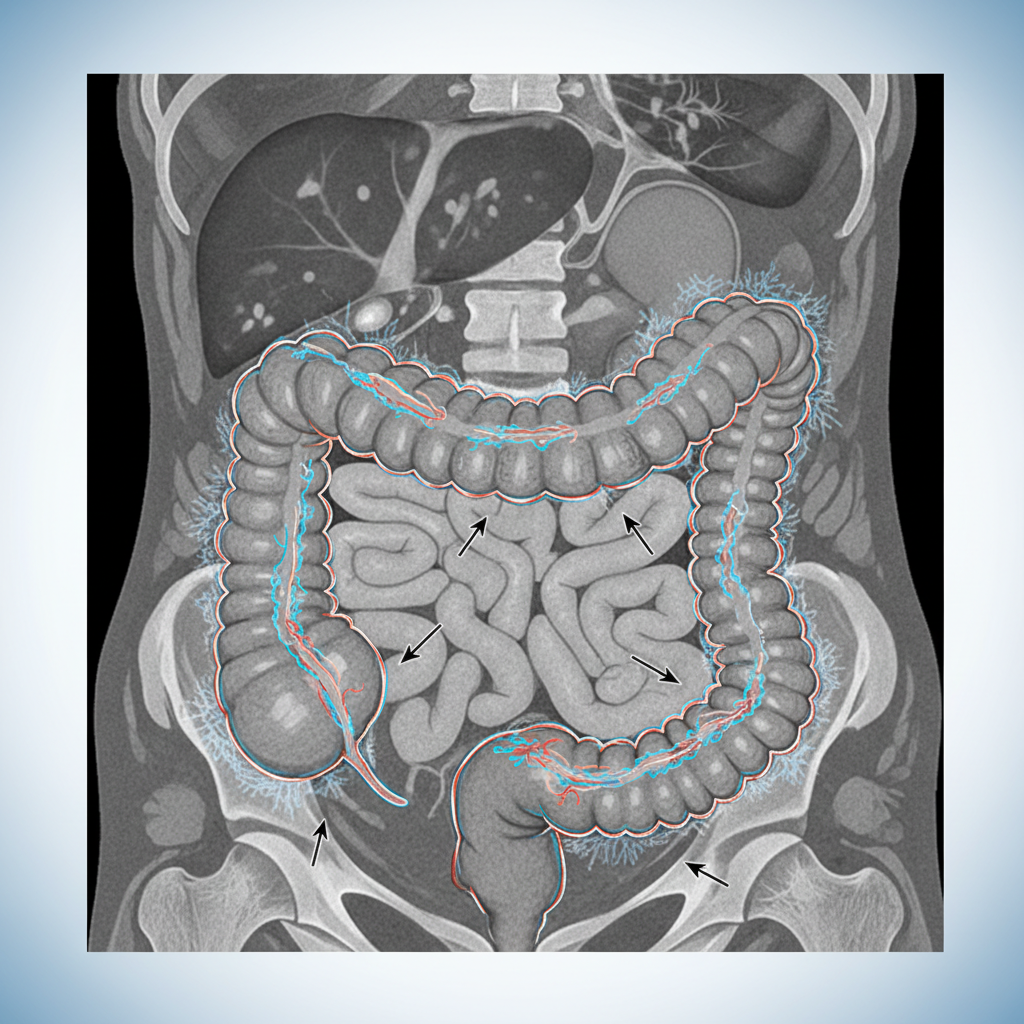

Imaging & Escalation

AXR: colonic thickening, no perforation

CT CAP: diffuse colitis